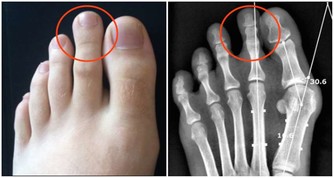

骨關節炎:軟骨磨損

骨關節炎:僵硬、疼痛、不能握拳、大拇指不靈活、有硬結

骨關節炎:X線檢查